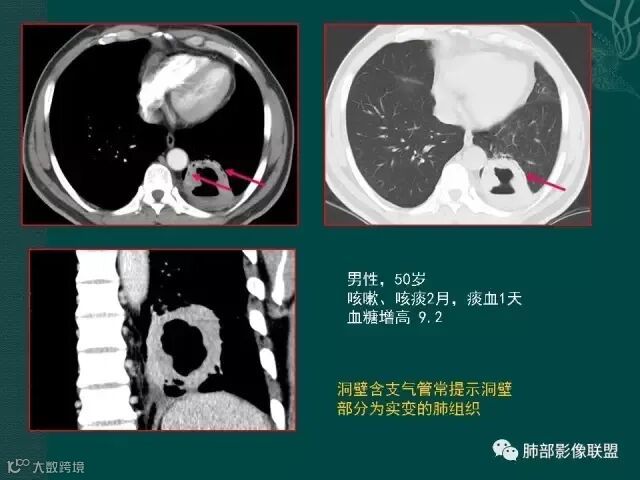

大片液化坏死,内多发空泡,初学者可能感觉是感染,但红箭头所指洞壁虽然不很厚,但仍可见到边界不清的低密度区,黄箭头所指病变侵犯胸膜。

定要记住,在免疫力低下,或白细胞降低的病人,如果在化疗过程中出现痰中带血,最大可能不是肿瘤进展,也不是侵犯血管,而是侵袭性的肺曲霉菌感染。

该病例进展较快,悬球征-霉菌感染的特异征象。